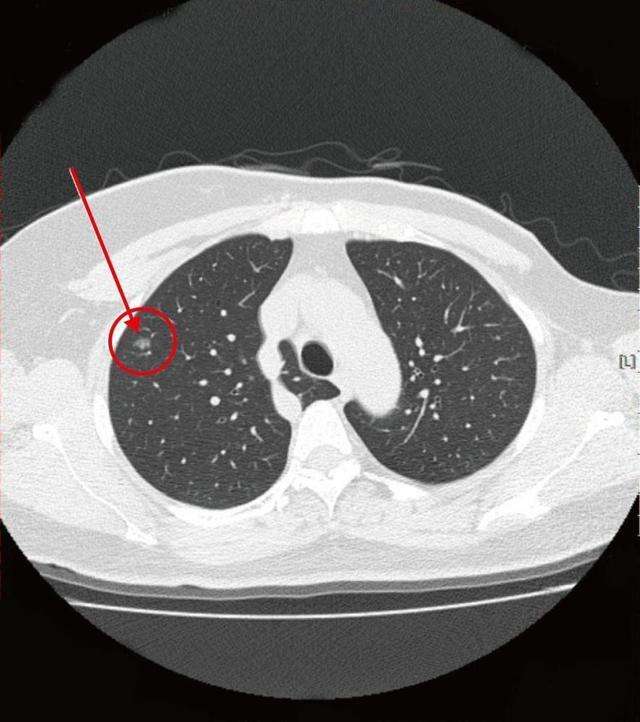

在临床中有很多患者都有相似的情况。现代医学认为,肺结节是CT影像学表现为直径≤3厘米的局灶性、类圆形、密度增高的实性或亚实性肺部阴影,可以为孤立性或多发性,不伴有肺不张、肺门淋巴结肿大和胸腔积液,这种病灶就叫肺结节。

找我看诊的刘女士经常咽喉发炎、上火、咳嗽,喉咙有红肿、滤泡,肺部CT检查显示结节多个,大小不一,最大的3~4毫米,肺内还有慢性炎症表现。我告诉刘女士她的结节多为炎症导致的可能性大,因此一定要注意日常饮食调理,同时要加上中医治疗,配合一个疗程的常规抗炎治疗,可以消除或者缩小结节。